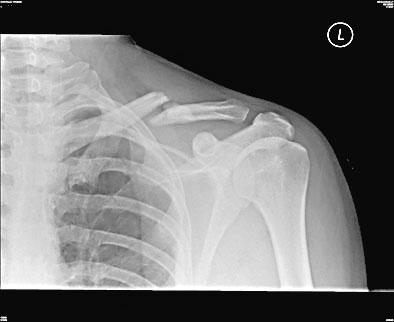

كسر عظم الترقوة (collarbone) في كتفي عندما تعرضت لحادث سيارة قبل أربعة أشهر. لكن عملية الشفاء بطيئة، وما زلت أشعر بألم في موضع الكسر، خصوصاً حين أحرك كتفي. هل هذا طبيعي، أم أني قد أضطر إلى الخضوع لجراحة إن لم يختفِ الألم؟

يصل عظم الترقوة الجهة العلوية من عظم الصدر، الذي يُدعى عظم القص، بعظم الكتف. ويُعتبر كسر الترقوة شائعاً، خصوصاً بين الأولاد والشبان. ويعود ذلك إلى أن الشبان يمارسون عادة رياضات تزيد من احتمال كسر عظم الترقوة، مثل كرة القدم، كرة السلة، المصارعة، الرغبي، الهوكي، والتزلج. نتيجة لذلك، تشكّل الإصابات الرياضية من الأسباب الشائعة لكسر عظم الترقوة. من الأسباب الأخرى السقوط وحوادث السيارات والدراجات النارية والهوائية.

إن لم تخضع للتصوير بالأشعة السينية منذ أن كسرت الترقوة، فقد يكون من الأفضل الخضوع لصور جديدة في هذه المرحلة للتحقق من تقدّم عملية الشفاء. يُشفى بعض كسور عظم الترقوة ببطء شديد، في حين أن بعضها الآخر قد لا يشفى البتة ويحتاج إلى علاج إضافي، مع أن هذه الحالة الأخيرة نادرة. لا شك في أن الكسور الكبيرة التي تؤدي إلى ابتعاد العظم عن موضعه أو تجعل قطع العظم المكسور تتداخل تتطلب جراحة لإعادة العظم على مكانه. ولكن في معظم الحالات الأخرى، لا تحتاج كسور الترقوة إلى جراحة، حتى وإن كانت تلتئم ببطء.